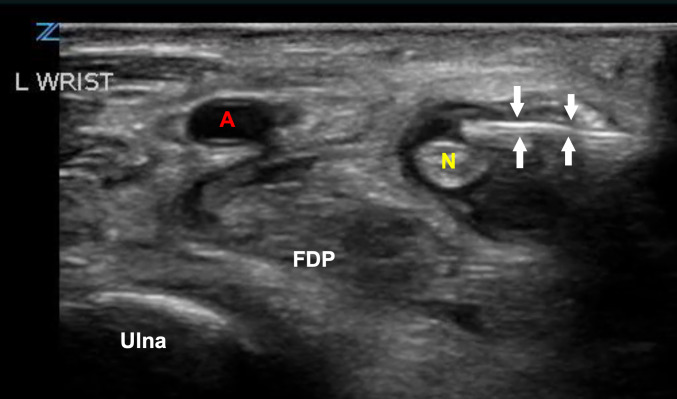

Performing an ultrasound-guided nerve block (UGNB) is now common practice in many emergency departments (EDs) and is considered a core skill according to the American College of Emergency Physicians (ACEP). Nerve blocks are mostly utilized for fractures and laceration repairs, however, these blocks have many other applications. We present a case of utilizing an ulnar UGNB in a patient with flexor tenosynovitis and a history of intravenous drug use (IVDU) when parental opiates proved to be ineffective.